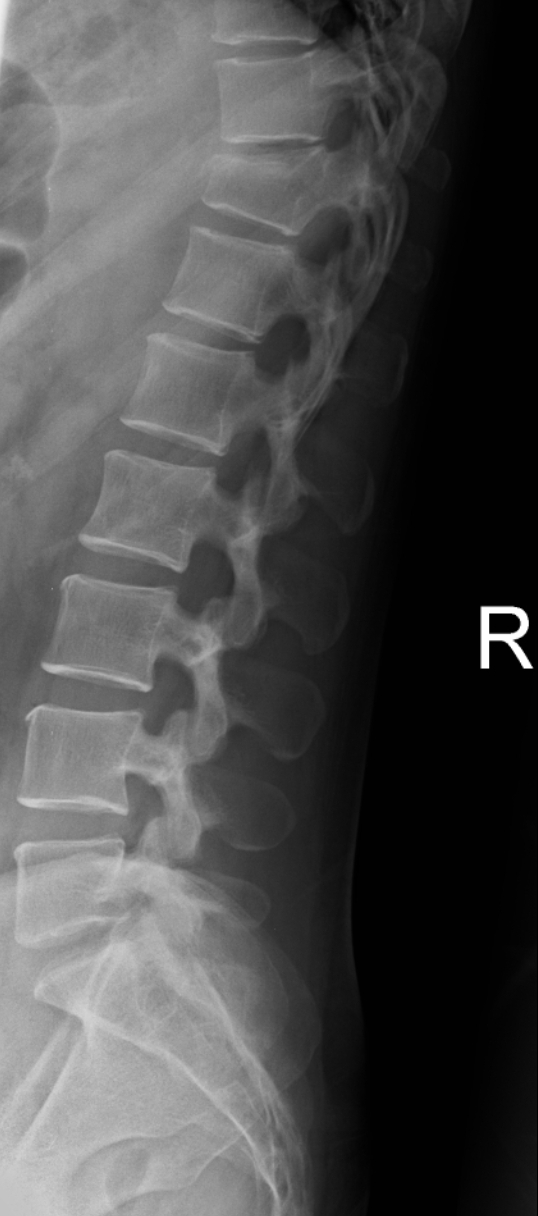

Male. Age 23. Builder.

Fell from a ladder. Lower back pain. Unable to move due to intense pain.

On examination: tenderness at the thoraco-lumbar junction.

What are your observations and conclusions?